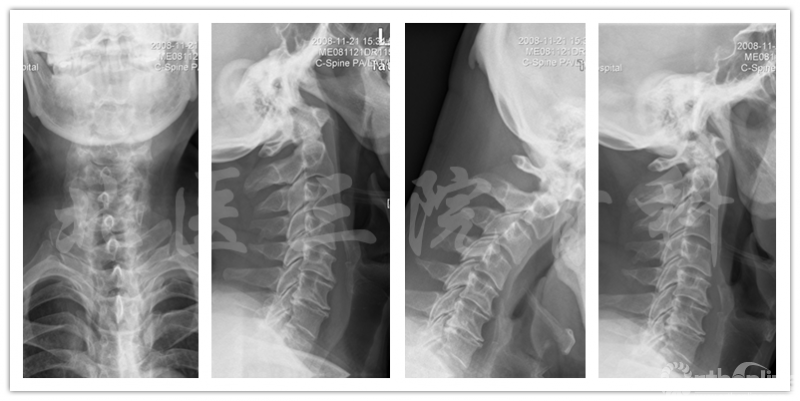

影像学检查

X线片

椎管测量

诊断:脊髓型颈椎病;颈椎间盘突出 (C3-C6);发育性颈椎管狭窄。